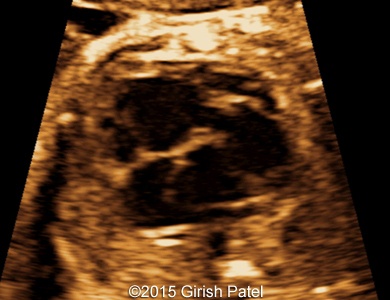

Following images and videos show a case of double inlet left ventricle with transposition of the great arteries that was seen at 26 and 36 weeks of otherwise non-complicated pregnancy.

Images 1, 2, 3, and 4: 2D images showing transverse scan of the heart with double inlet left ventricle and transposition of the great arteries. Following structures can be seen: dominant enlarged left ventricle (LV); diminutive right ventricle (RV) connected to the left ventricle via small bulboventricular foramen; both, left atrium (LA), and right atrium (RA) open to the left ventricle via separate tricuspid and mitral valves; foramen ovale flap can be seen within the left atrium; enlarged pulmonary artery (PA) arises from the left ventricle; small part of the aorta (Ao) arising from the diminutive right ventricle can be also seen.